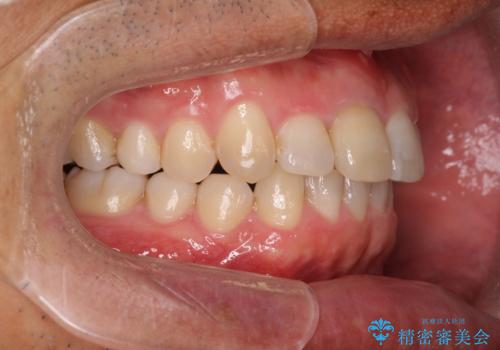

2級ディープバイト 遠心移動を伴うマウスピース矯正

・深い噛み合わせ(ディープバイト) ・2級性の咬合関係(上顎前突)・前歯のがたつき

深い噛み合わせと上顎前突の状態を治すのに時間がかかりましたが、治療後は理想的で安定した咬合関係となりました。